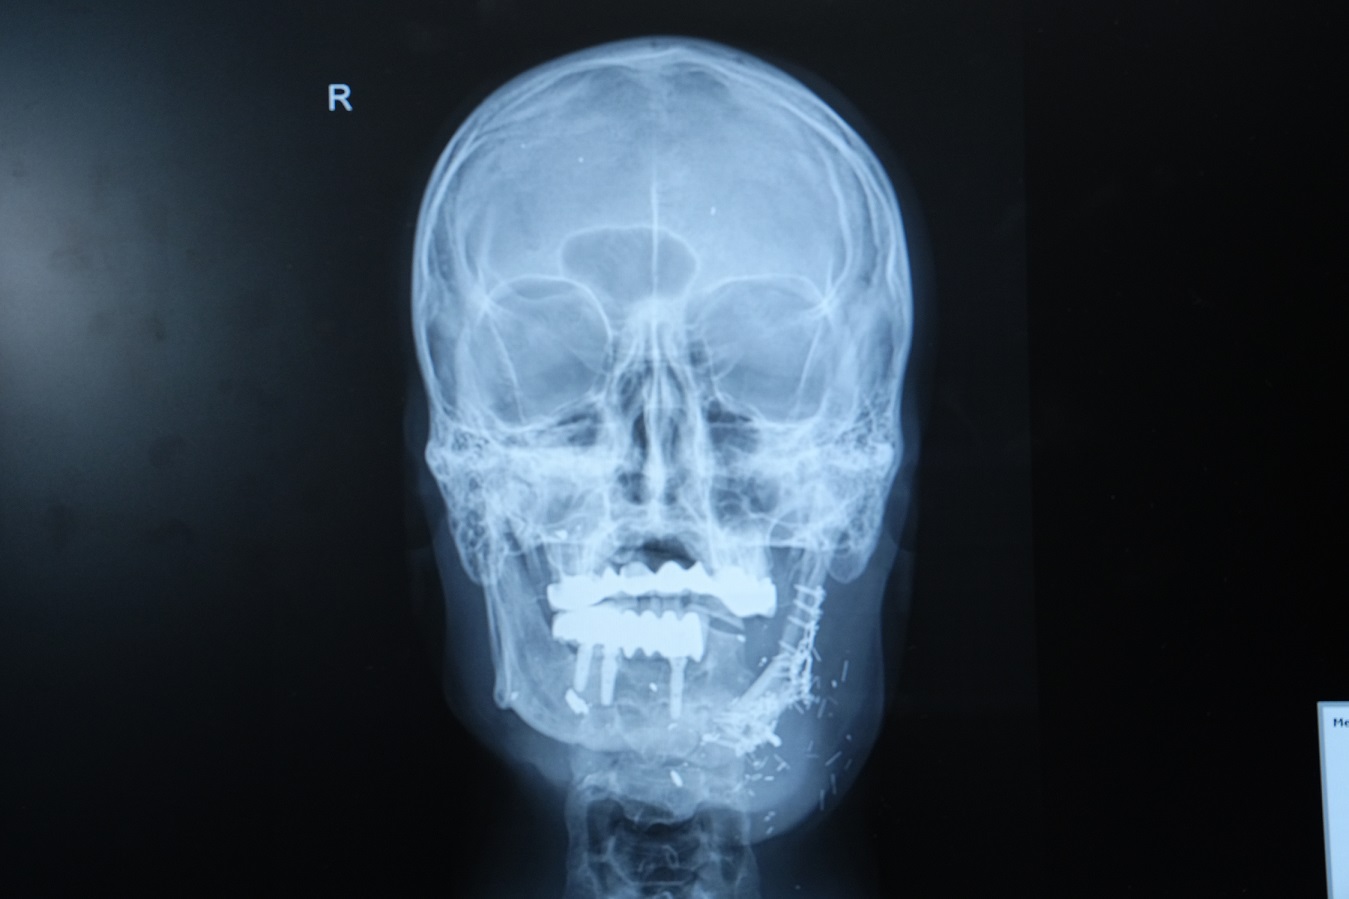

Bacağından aldığımız kemiği mikrocerrahi yöntemle çeneye naklettik, damar bağlantılarını yaptık ve plaklarla sabitledik.

Böylece hem fonksiyonel hem estetik açıdan başarılı bir sonuç elde ettik.”